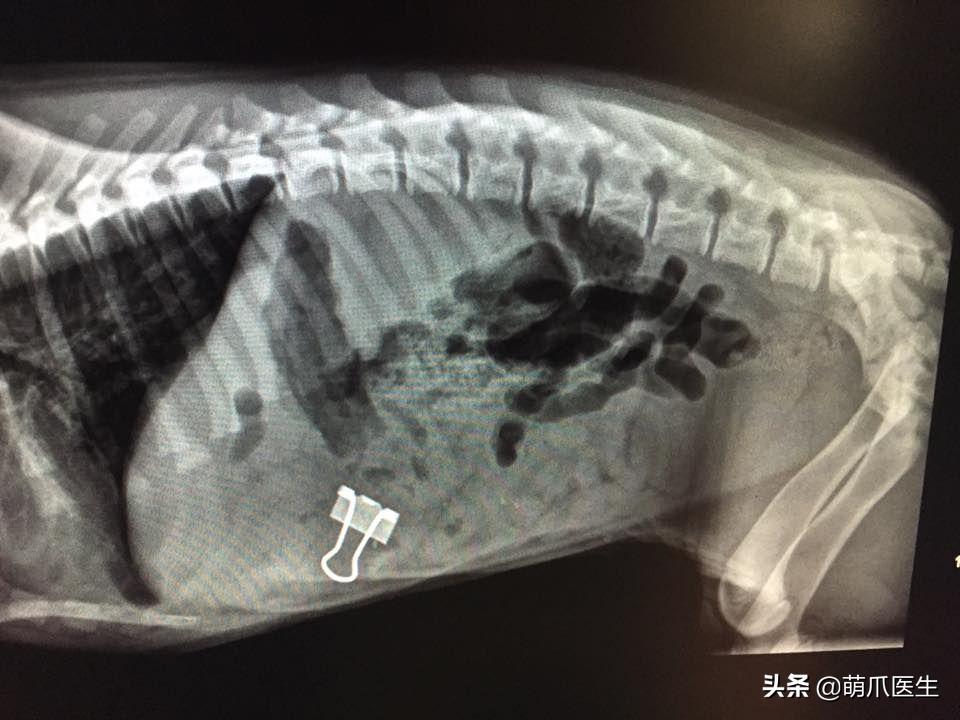

人们可以通过x光观察到猫咪体内的异物:

误食夹子的猫

█ 体内异物

X光片能看到猫咪体内是否有 高密度异物 ,包括被猫咪 误食吞下的各种奇葩物品,甚至更可怕的东西。

前几天就有新闻爆出,一只看似健康的猫咪在医院拍片后, 医生发现它体内被插入了15根针……